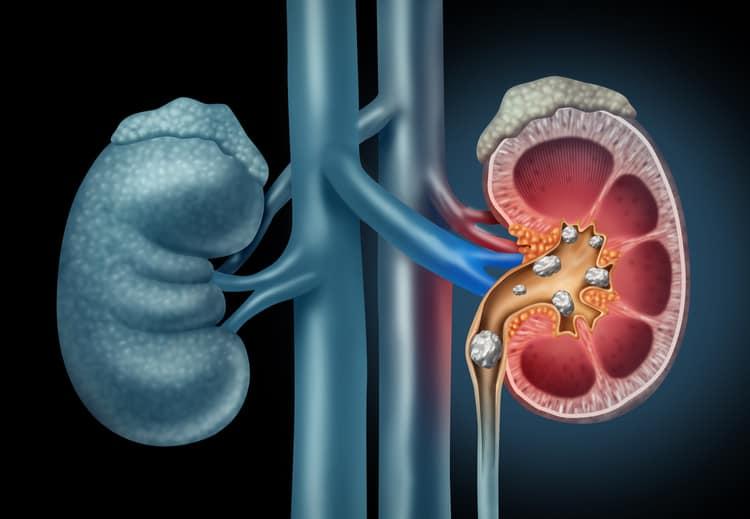

Sỏi thận là một tình trạng khá phổ biến hiện nay. Bác sĩ có thể kê nhiều loại thuốc trị sỏi thận khác nhau. Mỗi loại sẽ có những tác dụng riêng.

Bạn có biết hầu hết sỏi thận đều đi từ thận qua niệu quản đến bàng quang và cuối cùng đi qua niệu đạo? Tuy nhiên, bác sĩ thường yêu cầu điều trị để kiểm soát cơn đau khi sỏi di chuyển từ thận. Việc uống nhiều nước sẽ giúp cho sỏi di chuyển dễ dàng, nhưng một số người sẽ cần thuốc điều trị sỏi thận để giúp bệnh nhanh hết.

Nên uống thuốc trị sỏi thận hay mổ sỏi thận là một trong những câu hỏi được rất nhiều bệnh nhân quan tâm. Với sỏi thận đặc biệt lớn không thể tự di chuyển, sóng xung kích có thể được sử dụng để phá vỡ sỏi thành những mảnh nhỏ hơn. Thủ thuật này được gọi là tán sỏi. Ngoài ra, phương pháp điều trị phẫu thuật cũng có thể được thực hiện để loại bỏ sỏi nếu các phương pháp khác không thành công.

Phẫu thuật thông thường nhất là phẫu thuật nội soi niệu quản bằng tán sỏi laser. Thủ thuật này liên quan đến việc sử dụng một ống nhỏ để tiếp cận với sỏi, sóng laser làm vỡ các viên sỏi và một túi nhỏ để loại bỏ các mảnh.